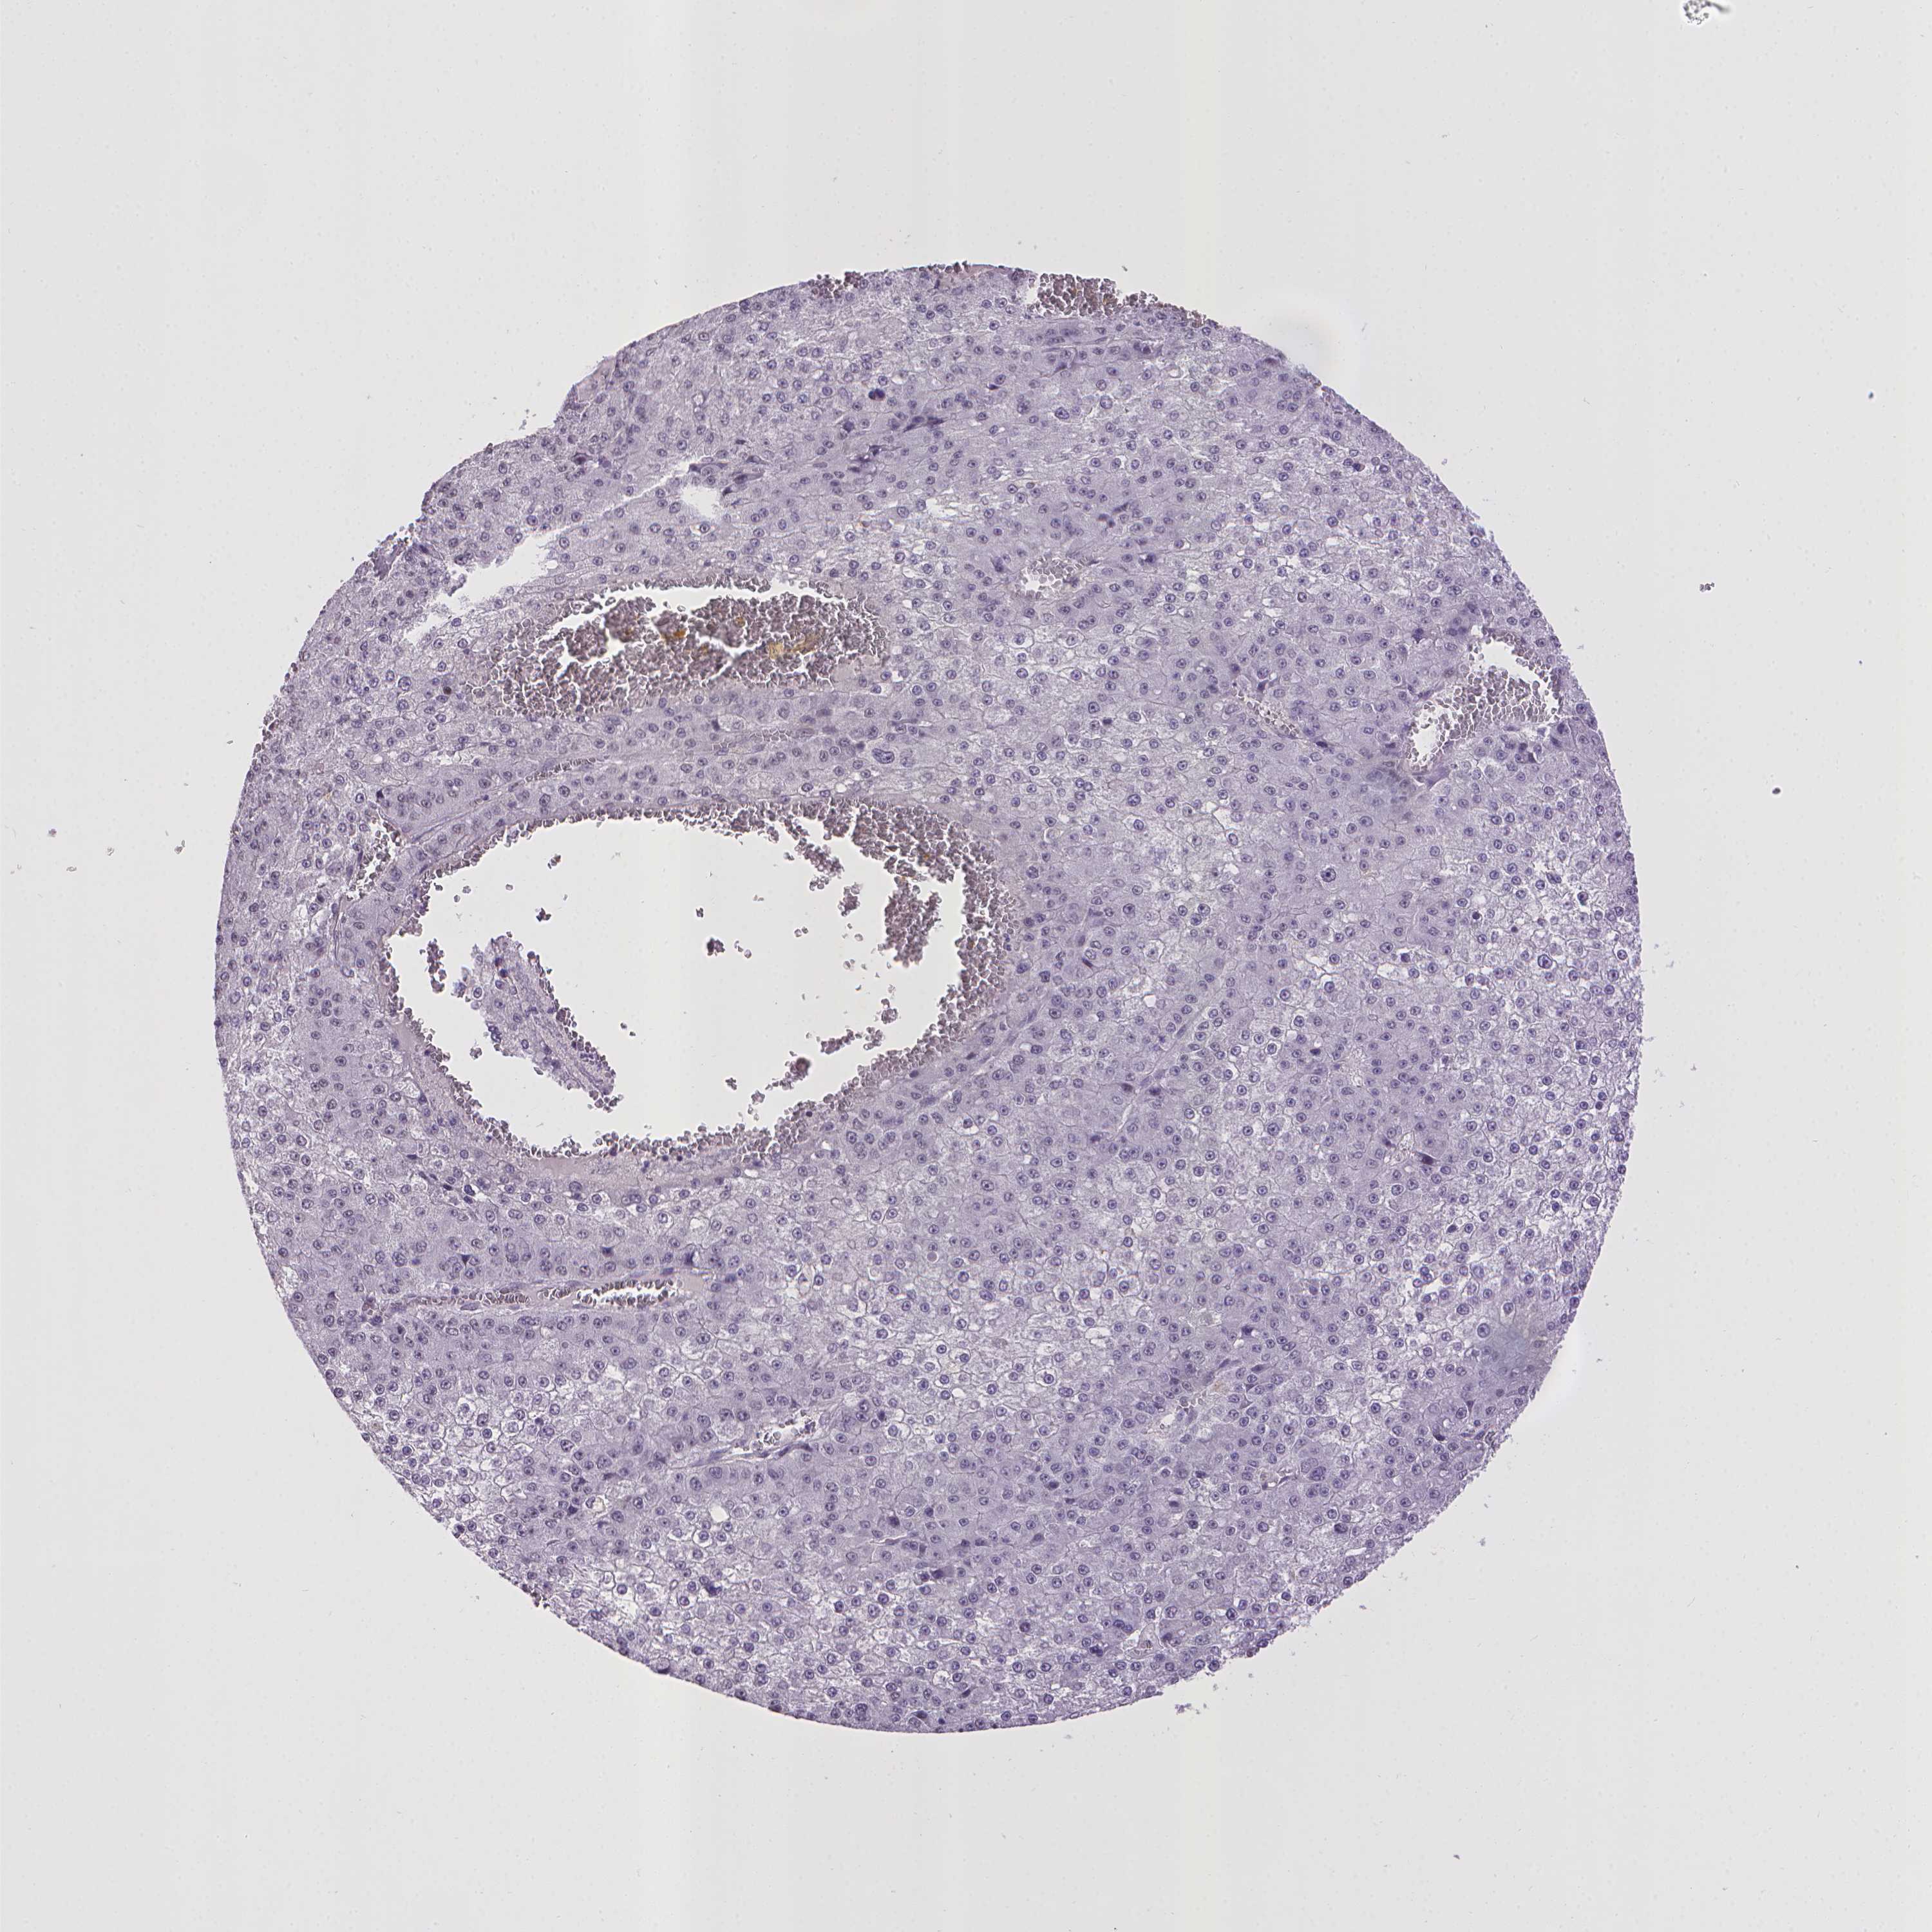

LIVER CANCER - Protein expressioni

A mouse-over function shows sample information and annotation data. Click on an image to view it in a full screen mode. Samples can be filtered based on level of antibody staining by selecting one or several of the following categories: high, medium, low and not detected. The assay and annotation is described here.

Note that samples used for immunohistochemistry by the Human Protein Atlas do not correspond to samples in the TCGA dataset.

Antibody stainingi

Antibody staining in the annotated cell types in the current human tissue is reported as not detected, low, medium, or high, based on conventional immunohistochemistry profiling in selected tissues. This score is based on the combination of the staining intensity and fraction of stained cells.

Each image is clickable and will lead to virtual microscopy that enables deeper exploration of all samples and also displays staining intensity scores, fraction scores and subcellular localization as well as patient and tissue information for each sample.

Antibody HPA031115

Antibody HPA056942

Staining

High

Medium

Low

Not detected

Intensity

Strong

Moderate

Weak

Negative

Quantity

>75%

75%-25%

<25%

None

Location

Nuclear

Cytoplasmic/membranous

Cytoplasmic/membranous,nuclear

Carcinoma, Hepatocellular, NOS

Cholangiocarcinoma